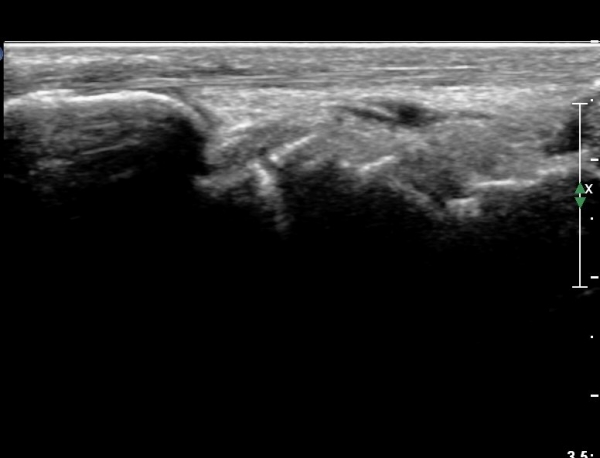

¼Õ¸ñ ÀåÃø ÁÖ»ó°ñ Á¾´Ü¸é °Ë»ç¿¡¼ ¹Ì¼¼ÇÑ ÁÖ»ó°ñ ÇÇÁú°ñ ¿¬¼Ó¼º ¼Ò½Ç(loss of cortical bone continuity)ÀÌ °üÂûµÊ(»çÁø 1, 2).

È®ÁøÀ» À§ÇÑ ÃÊÀ½ÆÄ°Ë»ç¿¡¼ ÁÖ»ó°ñ °ñÀý È®ÀÓ µÊ.